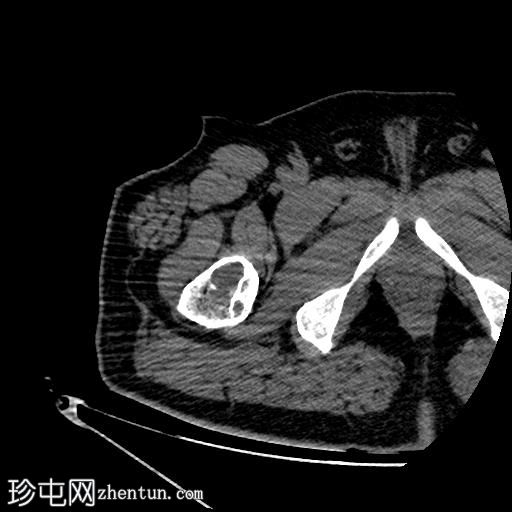

轴位骨窗

右股骨近端干骺端,股骨大转子下方可见一边界清晰的溶骨性病变。

未见皮质破坏及骨膜反应。

行CT引导下病变穿刺活检,术中及术后均未见并发症。